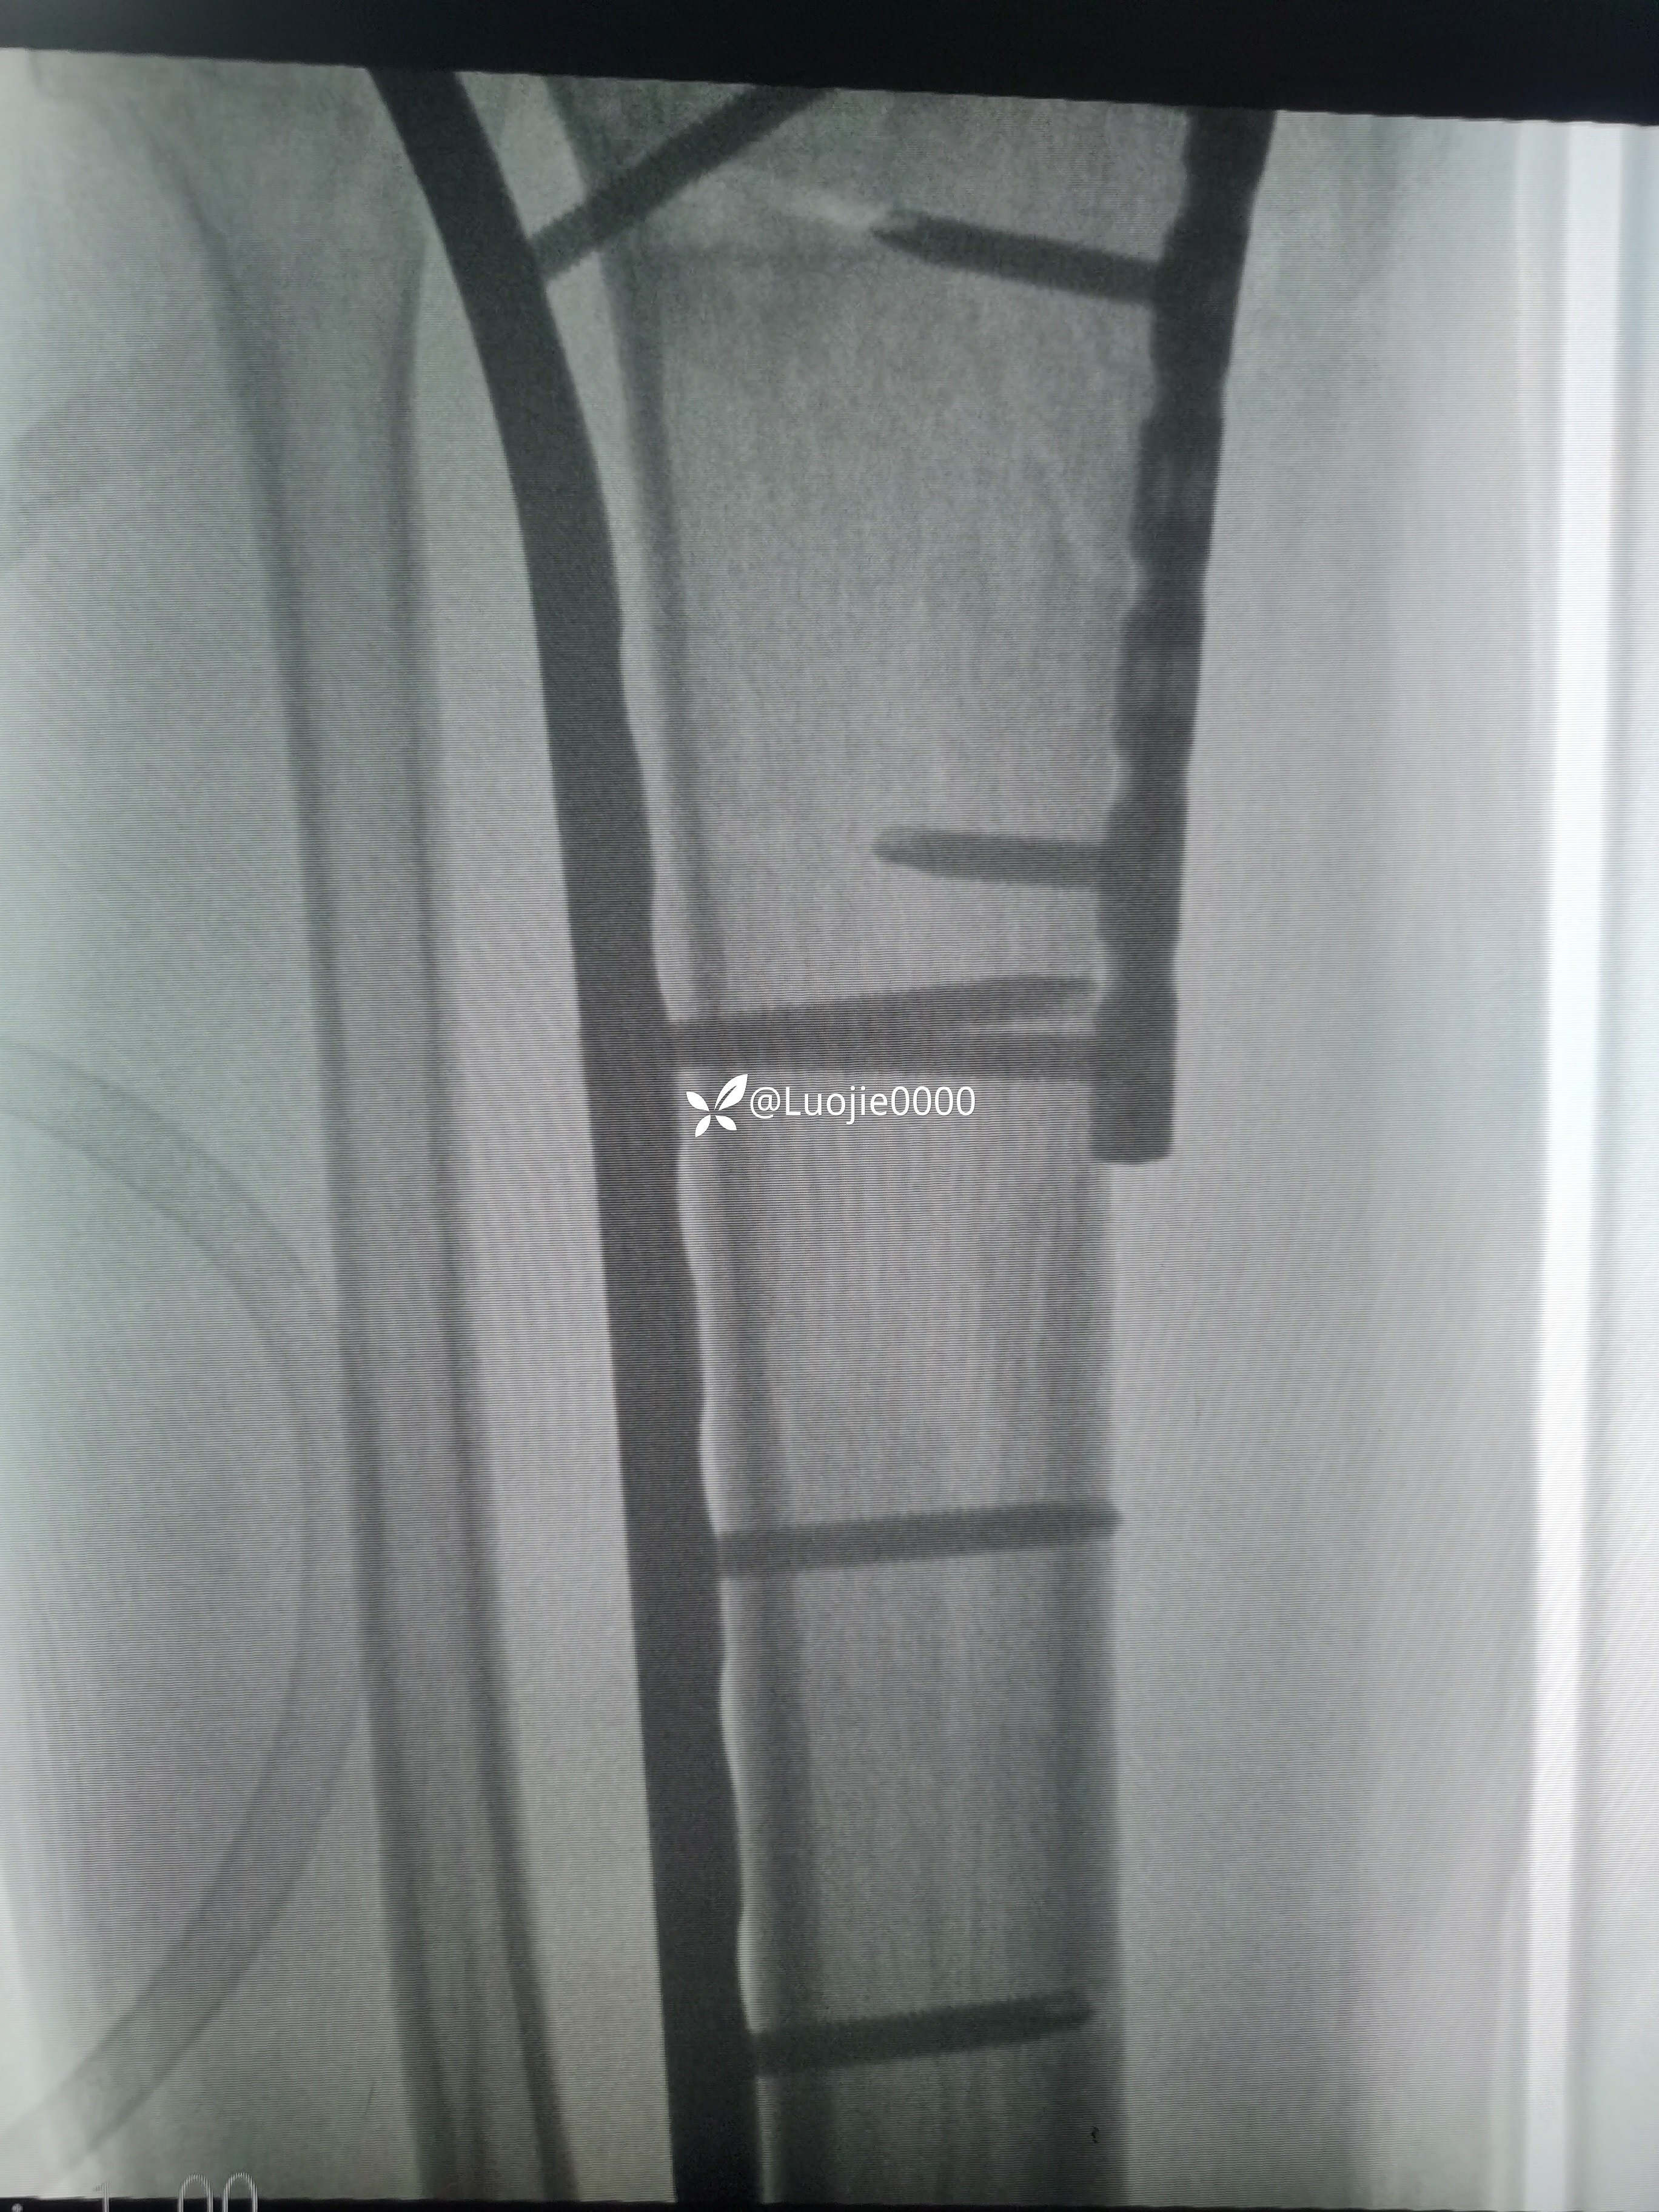

切开复的位

总结:1.理论指导临床,临床结合实际;